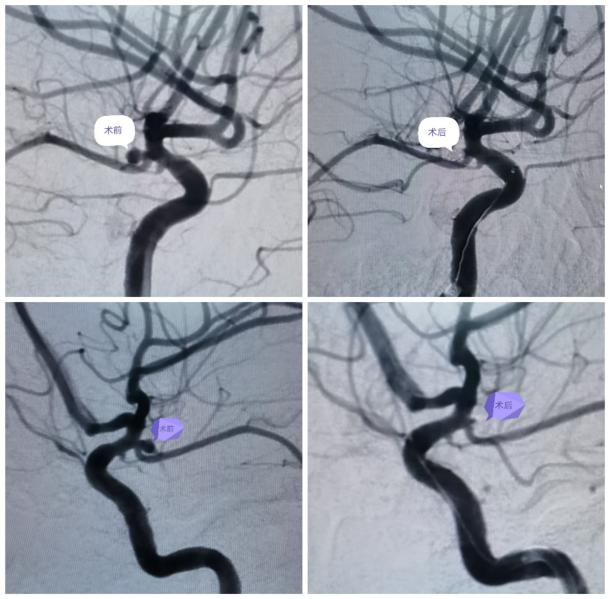

最近,患者苏女士突发意识不清,伴右侧肢体偏瘫,肌力1级,来我院急诊医学科就诊,头部CT提示蛛网膜下腔出血,Hunt-Hess(分级)3级。经神经外科荆泽林主治医师会诊后立即收住入院同时向科主任王伟志汇报患者病情,科室集体讨论后考虑颅内动脉瘤破裂致蛛网膜下腔出血,急行脑血管造影术。

术中证实术前判断正确,科主任王伟志、主任医师云亚滨、副主任医师陈波考虑左侧后交通动脉瘤破裂致蛛网膜下腔出血,征得家属同意,进一步行颅内动脉瘤栓塞术。

术前

术后

手术顺利,术后第3天患者意识清楚,对答正确,右侧肢体肌力4级,术后第5天患者已下地活动。